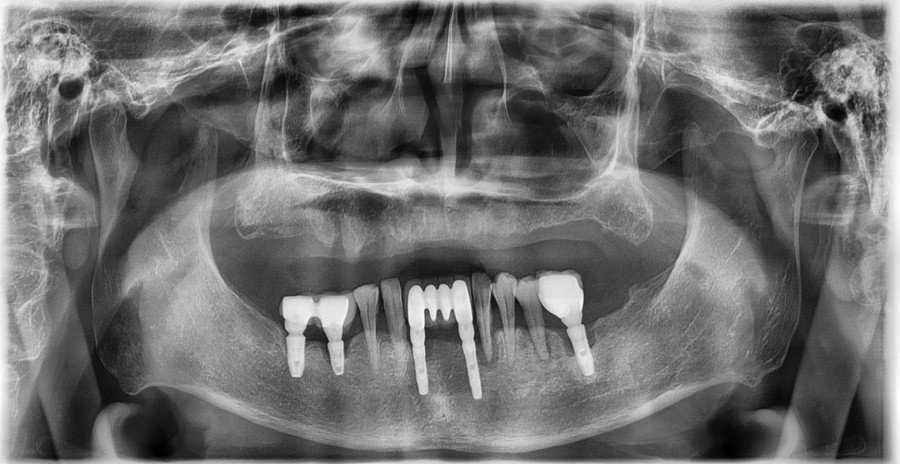

파노라마 X-ray와 구강 스캔을 통해

현재 잇몸 높이, 잇몸 두께,

턱의 움직임까지 확인했습니다.

상악은 지지할 치아가 전혀 없어서

부분틀니로는 안정적인 고정이 불가능했습니다.